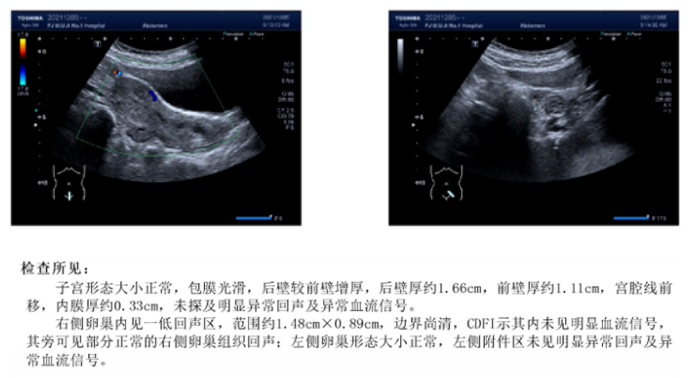

患者夏XX,女性,28岁,未婚。2019年02月门诊就诊。 主诉:痛经加剧3年余,发现盆腔肿物2月余。 现病史:12岁月经初潮,无痛经;3年余前出现痛经,尚可忍受;3年来痛经反复发作渐进性加剧,口服止痛药可缓解。2月余前外院体检彩超示:右侧卵巢肿物,巧克力囊肿待排(大小约4.1cm×3.7cm);建议手术治疗,患者因个人因素拒绝手术。2019.02.11就诊我院门诊,彩超示:子宫后方囊性肿物,巧克力囊肿?(大小约3.32cm×3.61cm)。就诊时VAS评分:7分。 既往史:体健,无药物、食物过敏史。 月经史:初潮12岁,7/30-33天,LMP:2019.01.29,月经量正常,痛经3年余(详见现病史),渐进性加剧,经期规律,白带无异常。 婚育史:未婚,有性生活史,0-0-0-0。 家族史:无内异症及恶性肿瘤家族史。 体格检查:T36.2℃,P73次/分,R19次/分,BP120/70mmHg。BMI 18.3kg/m2。腹软,无压痛、反跳痛,双下肢无浮肿。 专科查体:外阴阴道无异常;宫颈光滑,无举痛摇摆痛;子宫体:前位,常大,质地中等,无压痛,活动欠佳;右侧附件区:可扪及一肿物,囊性,直径约4cm,边界清,活动欠佳,无压痛;左侧附件区:未扪及肿物,无增厚及压痛。三合诊:直肠壁光滑,双侧骶主韧带无增厚,子宫直肠凹软,未扪及触痛性结节。 辅助检查: 2019.02.11妇科彩超示:子宫后方囊性肿物,巧克力囊肿?(大小约3.32cm×3.61cm)。 肿瘤标记物:CA125:52.40 U/ml;HE4:44.3 pmol/L;CA199:9.3 U/ml,AFP:1.50 ng/ml,CEA:0.58 ng/ml。 AMH:4.24ng/mL。 血常规、生化全套、凝血功能、DDI未见异常。 11.png